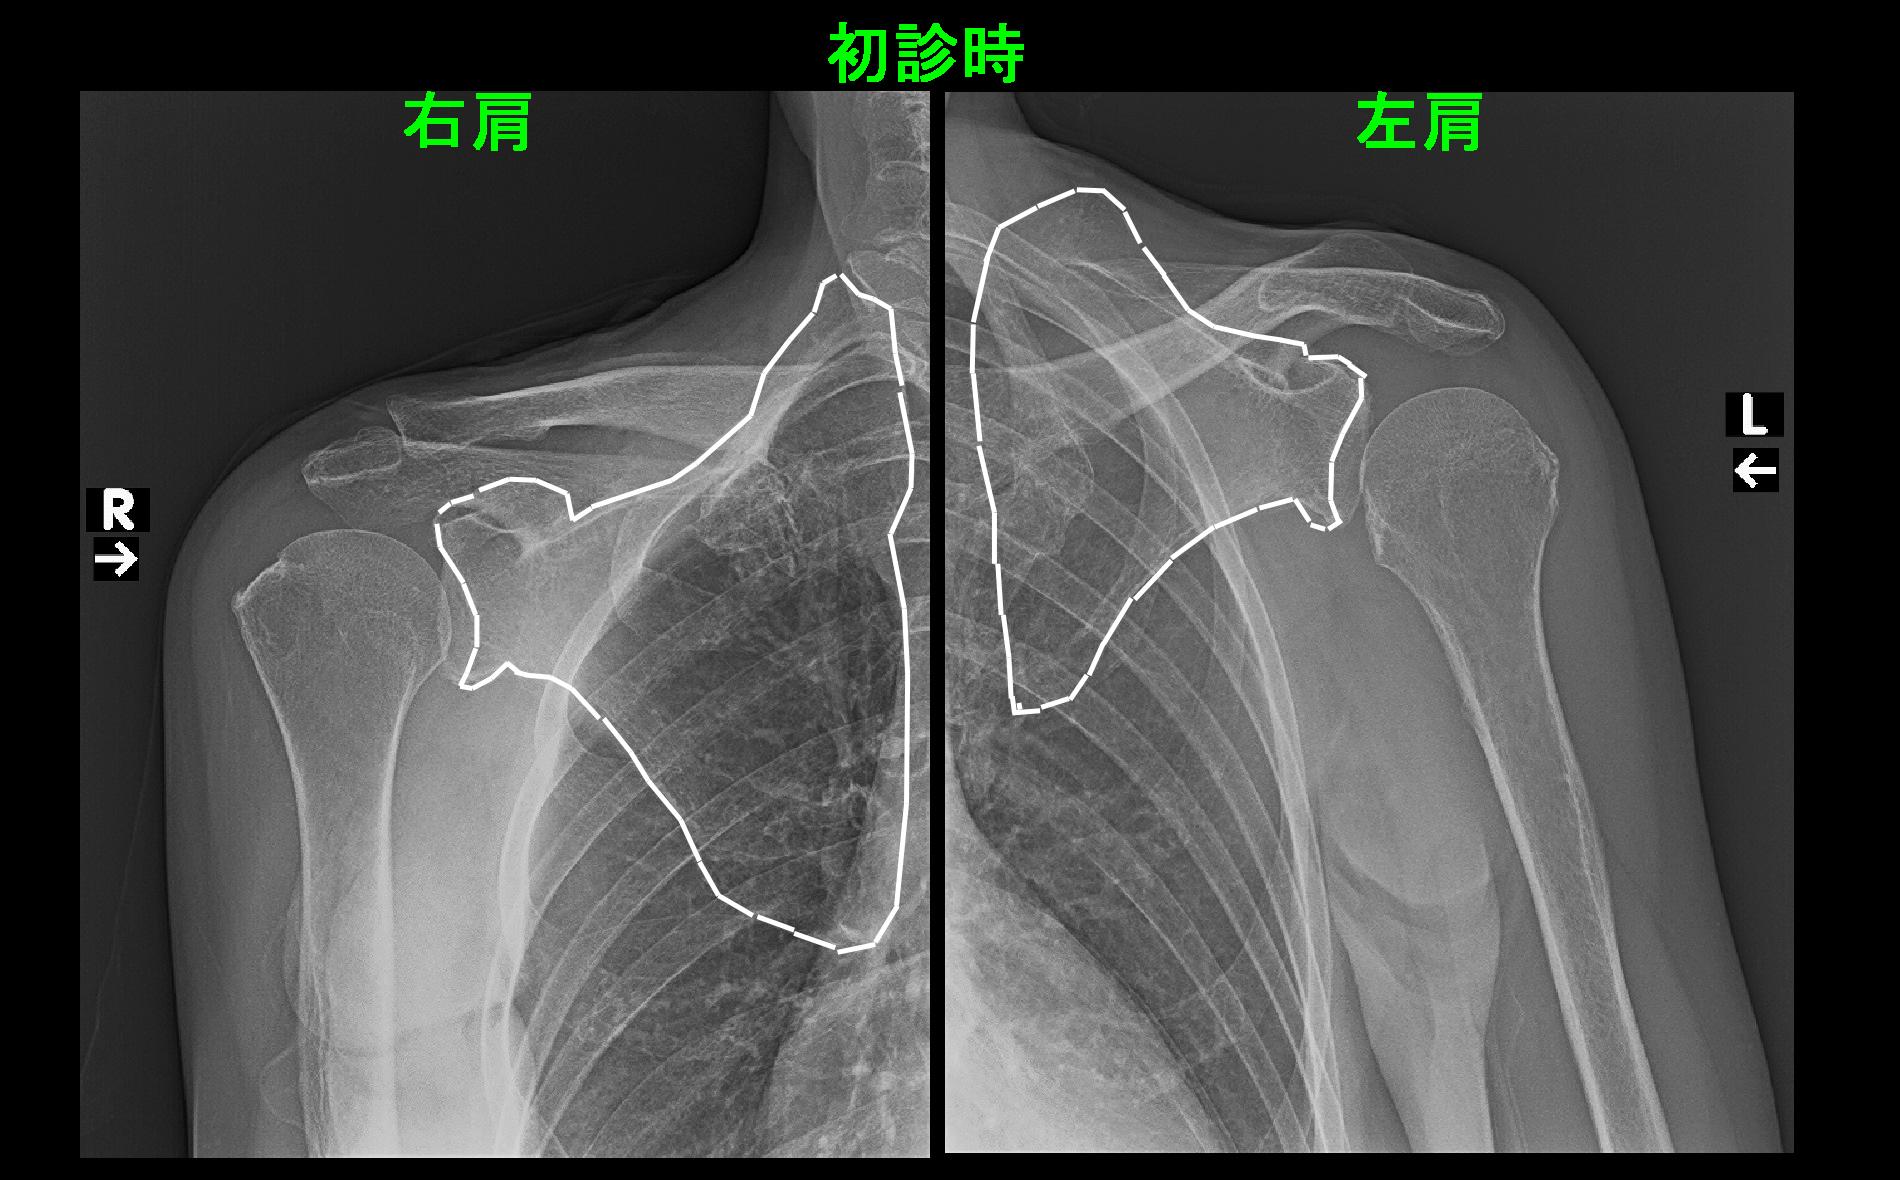

初診時の両側のレントゲン像ですが、肩甲骨は白線で囲っています。左肩甲骨は頭部側に偏位していて、縦の長さも短縮しています。

これは脳神経の副神経を損傷したことによって発生した左僧帽筋麻痺の状態で、甲状腺の手術ミスとしては有名なもので、医師であれば知らない人はいないはずです。

僧帽筋とは背骨から起きて肩甲骨に付着する大きな筋肉で肩甲骨を動かしていますが、僧帽筋が麻痺して肩甲骨を下に引っ張る力が大きく減弱し、左肩甲骨は頭部側に偏位してしまったのです。